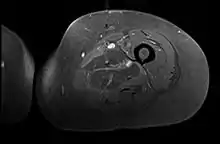

Creatine kinase may be normal or increased probably depending upon the stage of the condition when sampling is undertaken. ESR is elevated. Planar X-ray reveals soft tissue swelling and may potentially show gas within necrotic muscle, Bone scan may show non specific uptake later in the course. CT shows muscle oedema with preserved tissue planes (non-contrast enhancing). MRI is the exam of choice and shows increased signal on T2 weighted images within areas of muscle oedema. Contrast enhancement is helpful but must be weighed against the risk of Nephrogenic Systemic Fibrosis as many diabetics have underlying chronic kidney disease. Arteriography reveals large and medium vessel arteriosclerosis occasionally with dye within the area of tissue infarction. Electromyography shows non specific focal changes.